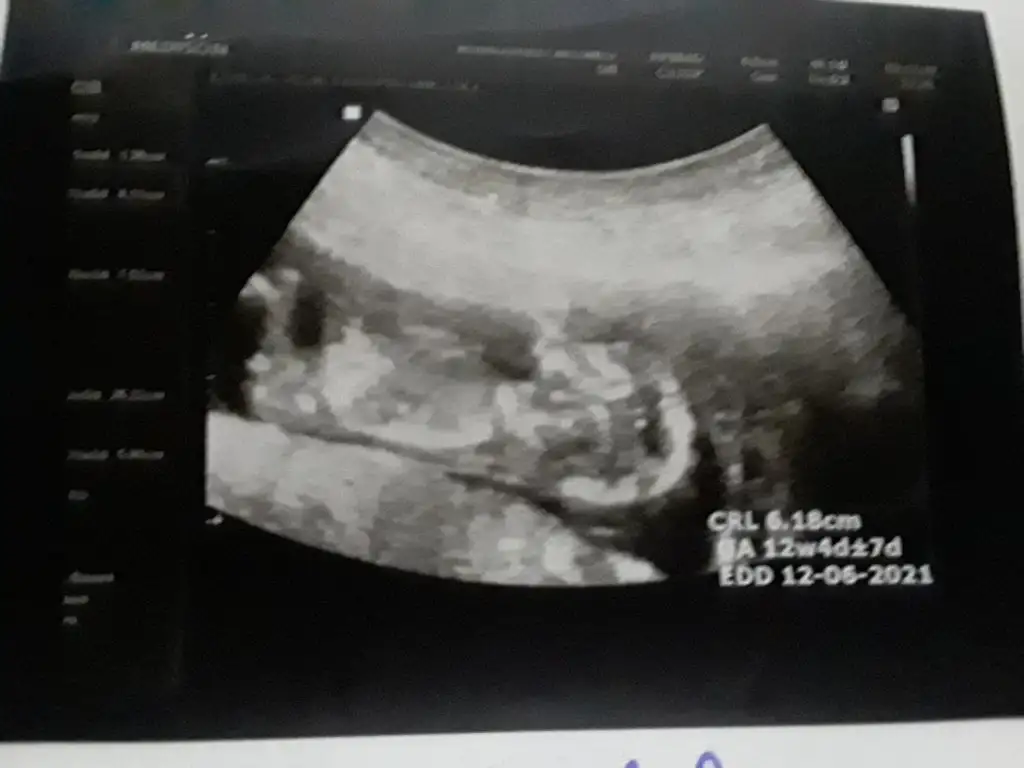

Erkeğe benziyor goruntusuKizlar 12 haftalik bebegimin cinsiyet tahmini yapar misiniz cok merak ediyorum :) Eki Görüntüle 2685687